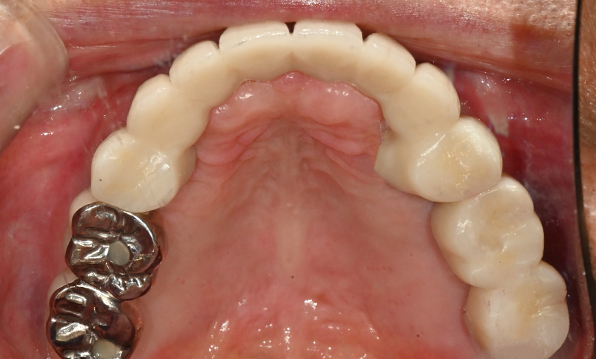

Before & After

| Before | After |